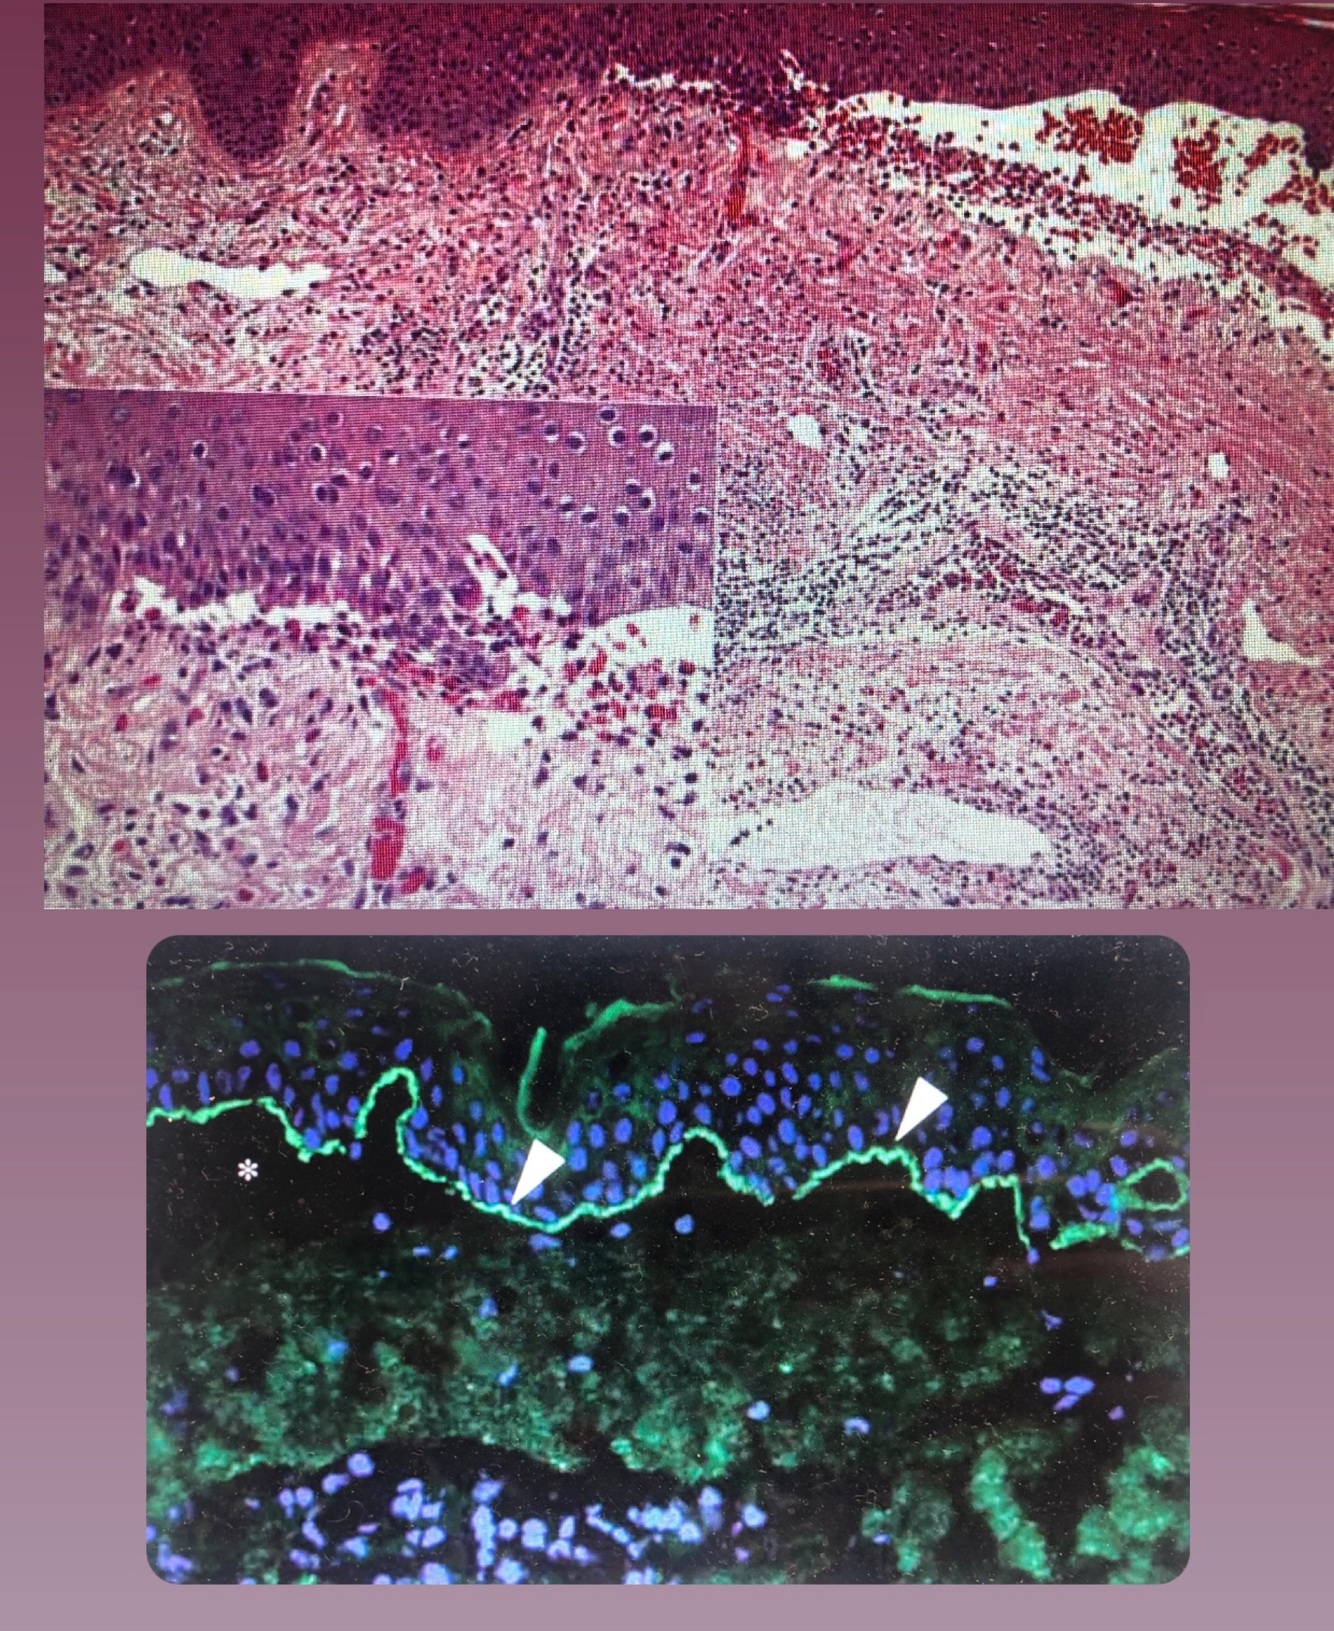

Qual o dx?

Penfigo paraneoplasico

• clivagem suprabasal

• degeneração hidrópica da camada basal com padrao liquenoide (dermatite de interface)

Penfigoide bolhoso

Ap: clivagem subepidermica, com neutrofilos e eosinofilos

Salt split skin: fluorescencia no teto da bolha